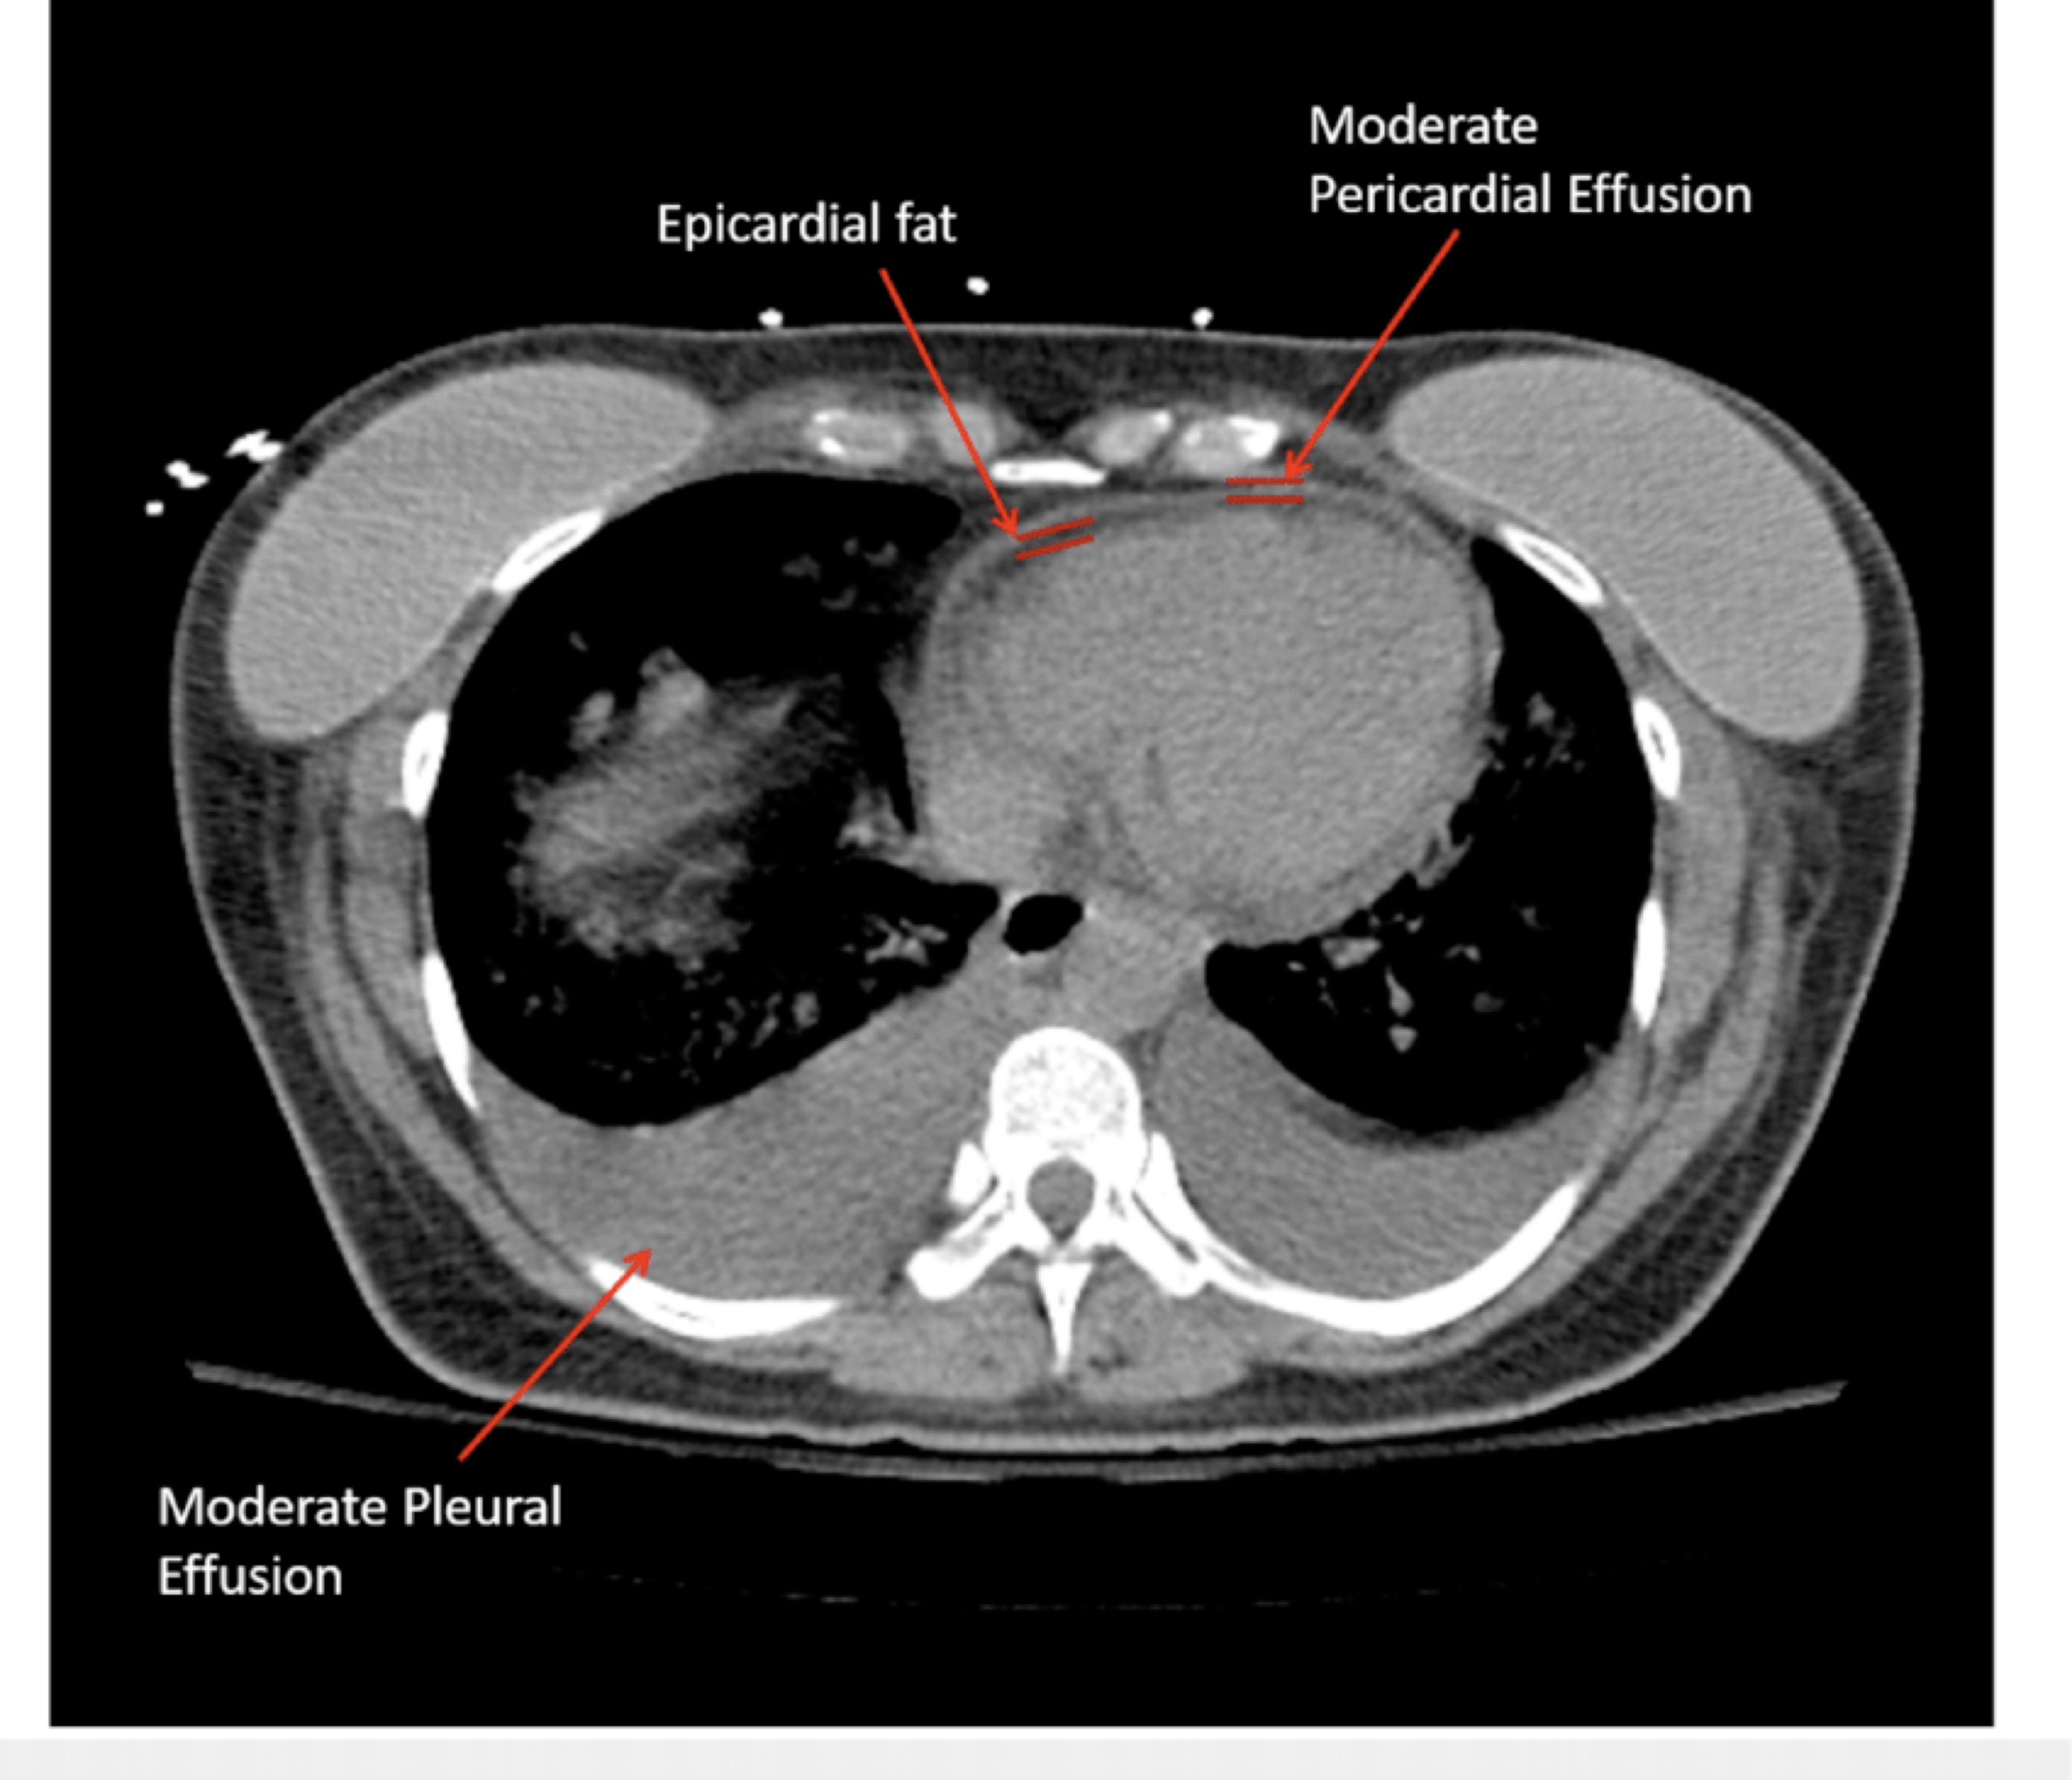

- Pericardial fat

- Pericardial fat appears “stippled” and is located in the anterior atrioventricular groove, best visualized in the parasternal long-axis (PLAX) *.

- In contrast, an effusion (usually anechoic) will typically collect in the most dependent pericardial location.

- It adheres to the myocardium and therefore moves in synchrony with the heart throughout the cardiac cycle.

- In contrast, an effusion will alternately appear smaller and larger as the adjacent cardiac chamber expands and contracts within the pericardium, whose space they share.

🔎 Epicardial fat vs. pericardial effusion.

- In CT, the density (HU) of epicardial fat vs pericardial effusion is shown below. In echo, see here 🎥.